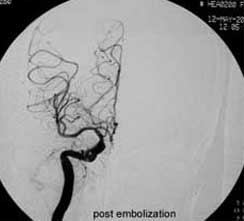

二、脑动静脉畸形(AVM)

---- Spetzler对AVM的分级方法已越来越多地被人们接纳和采用。脑AVM最危险的症状之一是出血。AVM每年的出血率为 3%~4%,第一年内再出血约6%。每次出血的致残率为30%,病死率为12.5%,而积极治疗的总残废率加病死率在10%以下。

---- 血管内栓塞对于单支或少数供血动脉的AVM,特别是新近出血的病例,可以达到微侵袭、痛苦小、疗效迅速的目的。 近来改变栓塞方式,将导管直接放置 畸形血管团内,注射NBCA胶,可使畸形团的解剖 治愈率提高至27%。再加上更细、超 滑的微导管问世,栓塞的并发症更为降低。针对大型、功能区 的AVM栓 塞可缩小其体积,改善血液动力学分布,以利于显 微外科技术切除或放射外科治疗,是后二者的重要辅助手段。

----立体定向放疗(γ-刀、χ-刀)对AVM是一种有希望的选择性治疗方法。据文献报道,AVM治疗后年消失率30%~50%,2年 消失率70%~90%,其消失速度与所用的照射量成正比,与AVM 的大小成反比。从治疗到AVM完全闭合之前每年的出血率 3%~4%,与自然出血史相同,所以对有出血史的患者,应优先采用栓塞或手术方法。大型AVM经若干次栓塞后体积缩小即可 放射治疗。但栓塞物质应是NBCA。其它颗粒或丝线栓塞,均有复发之虞。栓塞加立体定向放疗可使60%~80%的患者免于开颅 手术而获治愈。